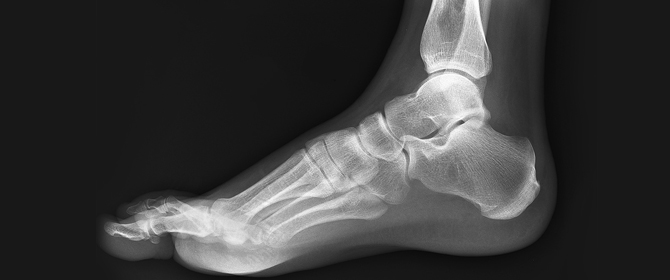

Our practitioners will then run through with you what will need to be done to help the problem and then you can ask questions about the treatment. Sometimes an x-ray exam is also needed so that the actual cause of the problem can be identified.

Post-Treatment Review. These allow the team to monitor your body and take place regularly to see how you’re going. If appropriate, x-rays are examined pre- and post-treatment to ascertain the amount of structural correction that has occurred.